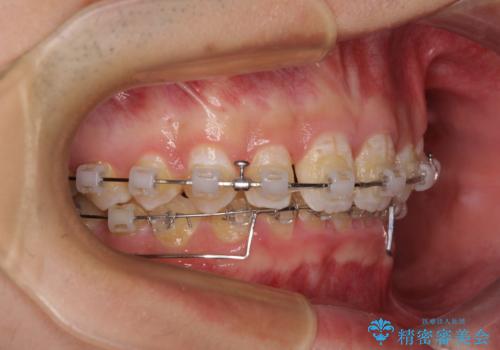

前方に移動している上顎臼歯を補助装置にて遠心移動させることで1歯対2歯の臼歯咬合を目指し、同時に深い咬合を改善していくこととしました。

このような咬み合わせの場合、治療期間は2年以上がかかることが一般的で、3年程度かかることもありえるケースです。

強く深い咬み合わせにより下顎装置は頻繁に脱離するため、治療期間が長くなりますが、予定通りに終了させることができました。